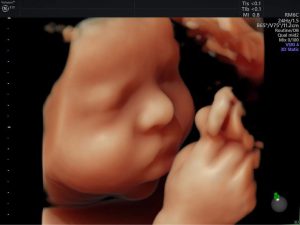

Mẹ đã nghe nhiều về siêu âm tim thai, vậy mẹ có nắm được những ...